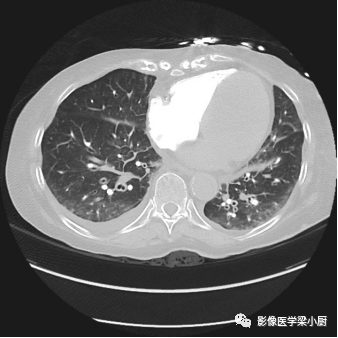

图片

心源性肺水肿,上肺野血管纹理增多,肺内血流重新分布,心影增大,双侧胸腔积液。